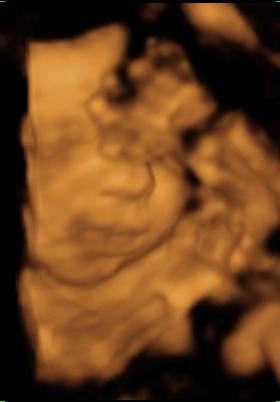

Kép Kép

No, hát ő lenne Noel baba 28 hetes nagyfiúként :) Amúgy a cukrom teljesen jó lett, nálam más miatt lehet több a magzatvíz. De azt olvastam, hogy a magzatvíz mennyisége egy napon belül is sokat változik, lehet éppen a csúcsot kapta el... Majd jövő héten kiderül mindenesetre